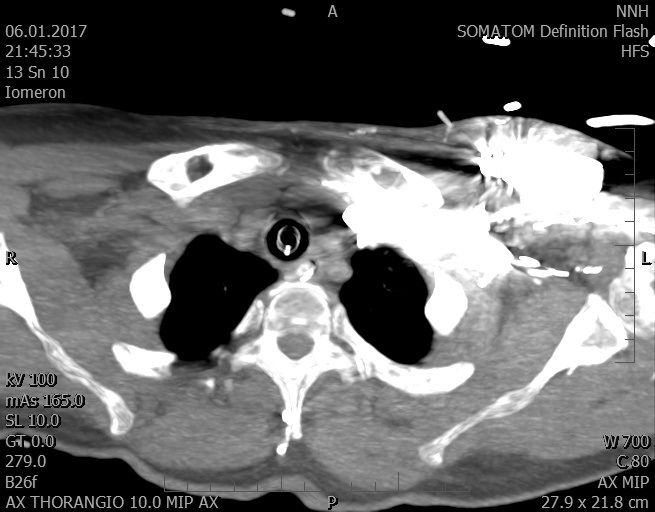

Video 1 - Akutní koronarografie prokázala normální nález na věnčitých tepnách s výjimkou suspekce na lehký spasmus na pravé koronární tepně.Echokardiograficky byla zjištěna těžká dysfunkce dilatované levé komory s nezvětšenou pravou komorou (video 2).

Video 2 - Echokardiograficky byla zjištěna těžká dysfunkce dilatační levé komory s nezvětšenou pravou komorou.Pro nejasnou příčinu zástavy jsme provedli i vyšetření výpočetní tomografií (CT), které vyloučilo plicní embolizaci (série 1 - soubory na konci článku). V den přijetí při přetrvávající oběhové nestabilitě byla nemocná opakovaně defibrilována pro fibrilaci komor se stabilizací rytmu po podání amiodaronu a mesocainu. Dle hemodynamických měření se jednalo o těžký kombinovaný šok. Vstupní laboratorní vyšetření bylo bez větších pozoruhodností. Posléze jsme doplnili anamnézu od příbuzných a zjistili, že pacientka užila do dvou hodin před srdeční zástavou první tabletu amoxicilinu na lehký respirační infekt. Při nevýtěžnosti vstupních vyšetření a nových anamnestických informacích jsme doplnili 14 hodin po kolapsu vyšetření koncentrace tryptázy v séru, která byla extrémně zvýšena (tabulka 2), což nás vedlo k podezření na anafylaxi.